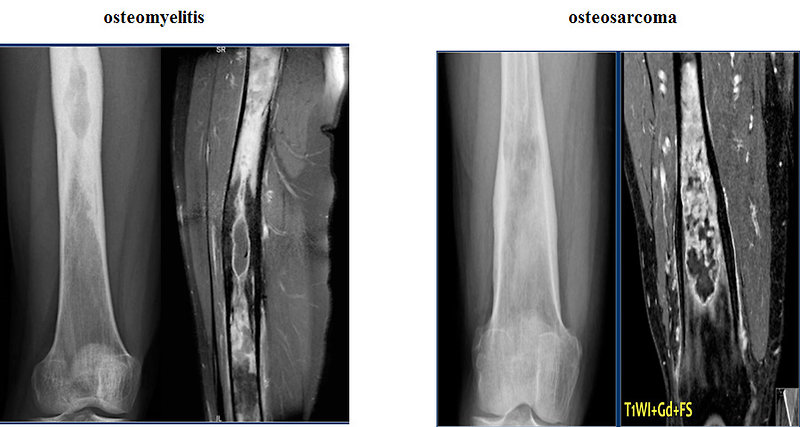

Как правило, на начальном этапе пациенты обращаются к врачам-травматологам.

И первым исследованием, позволяющим заподозрить саркому Юинга, становится рентгенография пораженной кости. Для данного патологического процесса характерно сочетание реактивного и деструктивного процессов костеобразования. Контуры кортикального слоя нечеткие, определяется расслоение и разволокнение кортикальной пластинки.

При вовлечении в процесс надкостницы на рентгенограмме выявляются мелкие пластинчатые или игольчатые образования. Кроме того, на снимках видна область изменения мягких тканей, по своему размеру превышающая первичную костную опухоль. При этом мягкотканный опухолевый компонент отличается однородностью, хрящевые включение, очаги обызвествления или патологического костеобразования отсутствуют.

При выявлении типичных рентгенологических признаков саркомы Юинга больного направляют в отделение онкологии, где проводится расширенное обследование для оценки состояния первичного очага и выявления метастазов. В ходе такого обследования выполняется компьютерная томография или магнитно-резонансная томография костей и мягких тканей, пораженных злокачественным процессом.

Данные исследования позволяют точно определить размер новообразования, степень его распространения по костно-мозговому каналу, связь с сосудисто-нервным пучком и окружающими тканями.